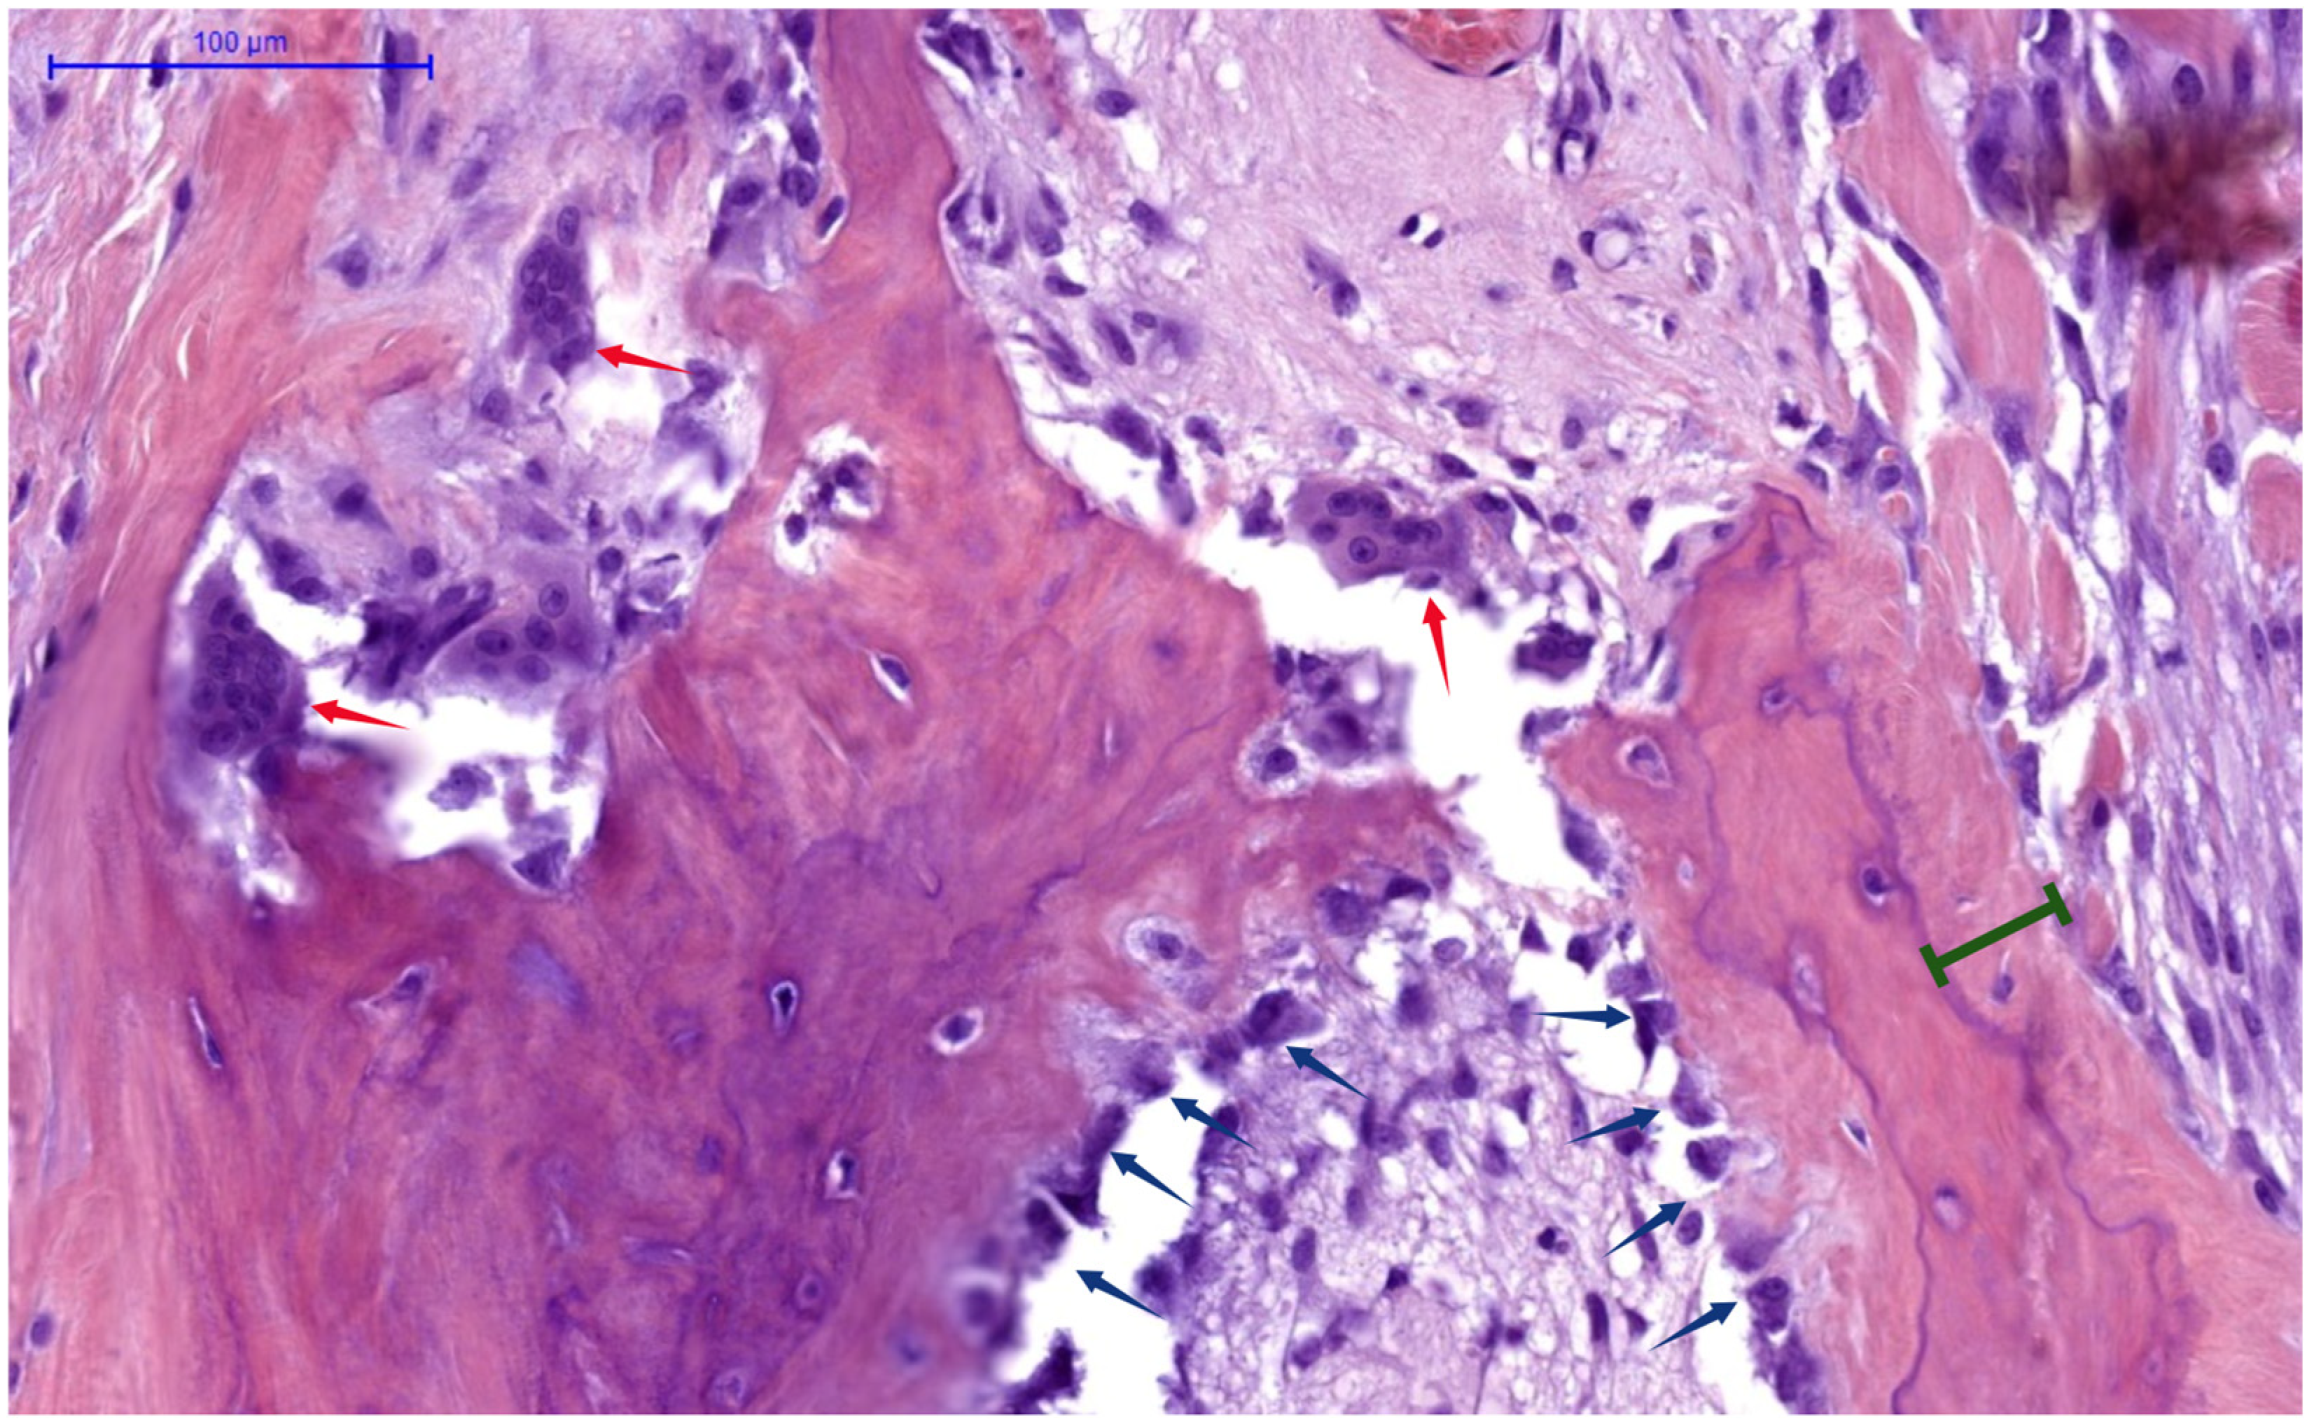

Figure 2 provides histological evidence of these cellular activities, demonstrating active human bone remodeling sites, with the following pathognomonic elements: osteoclasts (indicated by red arrows) actively resorbing bone matrix; osteoblasts (blue arrows) laying down new osteoid; and osteoid seams (green interval lines), which represent newly deposited bone matrix, awaiting mineralization.

Histological human bone section (H&E stain) demonstrating high-turnover remodeling. Multinucleated osteoclasts (red arrows) in resorption lacunae, are actively breaking down bone matrix, while osteoblasts (blue arrows), lining trabecular surfaces, are depositing osteoid seams (green bracket). NB: Archival image from Histology slide bank, processed in Biorender [].

In SHPT, chronic PTH elevation profoundly disrupts this orderly process. The activation frequency of new BMUs increases dramatically, from the normal 0.1–0.2/year to as high as 2–3/year in severe cases []. The resorption phase becomes accelerated and exaggerated, with osteoclasts creating abnormally deep resorption cavities (see Figure 2). Histomorphometric analysis reveals classic features of osteodystrophy: increased osteoclast numbers (often 10–20× above normal), extensive resorption surfaces (>15% compared to normal <2%), peritrabecular fibrosis, and woven bone formation—unmineralized osteoid seams [], as seen in Figure 2. Additionally, marrow fibrosis and formation of brown tumors occur in severe cases. Despite compensatory increases in osteoblast numbers, the rate of bone formation cannot match the accelerated resorption, leading progressively expanding osteoid volume, net bone loss and architectural deterioration [].